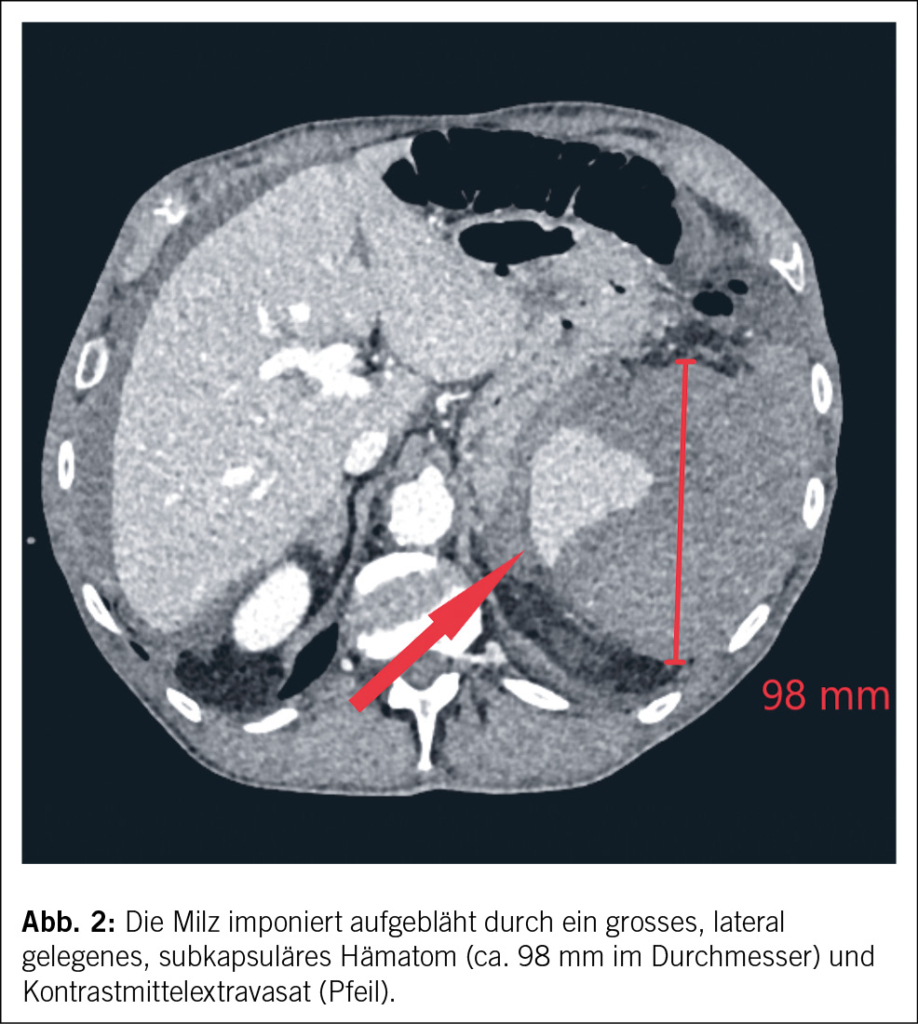

In der Computertomographie (Abb. 1) konnte intraabdominal viel freies Blut dokumentiert werden. Ätiologisch zeigte sich eine Milzblutung mit grossem subkapsulärem Hämatom und eine aktive Blutung der Milz in die Bauchhöhle (Abb. 2 und 3), entsprechend einer Verletzung Grad IV nach der American Association for the Surgery of Trauma (AAST) grading scale for splenic lacerations (7). Diese Einteilung richtet sich nach der Grösse des subkapsulären Hämatoms, dem Vorhandensein eines Kapselrisses, dem Ausmass der Organlazeration und dem Vorhandensein einer aktiven Blutung.